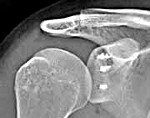

Установлено, что развитию данной патологии способствует повреждение суставной губы (повреждение Банкарта). Суставная губа является волокнисто-хрящевым образованием, которое прикрепляется к суставной впадине лопатки, делая вогнутую поверхность плечевого сустава более глубокой и препятствуя разобщению головки плеча и впадины лопатки при интенсивных движениях. Кроме того, у больных с привычными вывихами часто наблюдаются заднебоковые дефекты головки плечевой кости, обусловленные компрессионным переломом, не выявленным во время первичного травматического вывиха.

Предрасполагающими факторами являются отсутствие иммобилизации, неполноценная или слишком кратковременная иммобилизация, а также наличие ранних физических нагрузок. В подобных случаях поврежденные во время травматического вывиха мягкотканные структуры сустава не успевают полноценно восстановиться. Образуются участки несращения и грубые стойкие рубцы. Возникает мышечный дисбаланс, сустав становится нестабильным. Вероятность развития привычных вывихов также увеличивается при определенных индивидуальных особенностях строения плечевого сустава, например, слабовогнутой, плоской суставной впадине.